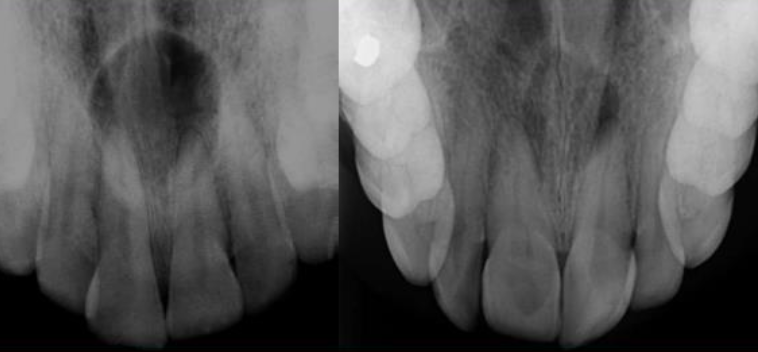

| Odontogenic Keratocyst cyst (OKC) |

|

下顎骨後端,下齒槽管上方 | 10-40y | 組生齒(40%) | |

| Radiolucent、 MD方向下顎骨吸收,但牙根完整。  |

|||||

| 4-8 層、副角化(有核)、Basal cell 為 palisaded(柵狀) | |||||

| 高復發 (30%) | |||||

| Periapical(radicular) cysts | Rest of Malassez 被刺激 | - | - | true/ periapical cyst 圓形的光通性包圍根尖 |

牙根吸收, 2cm ↑ 根管治療無效  |